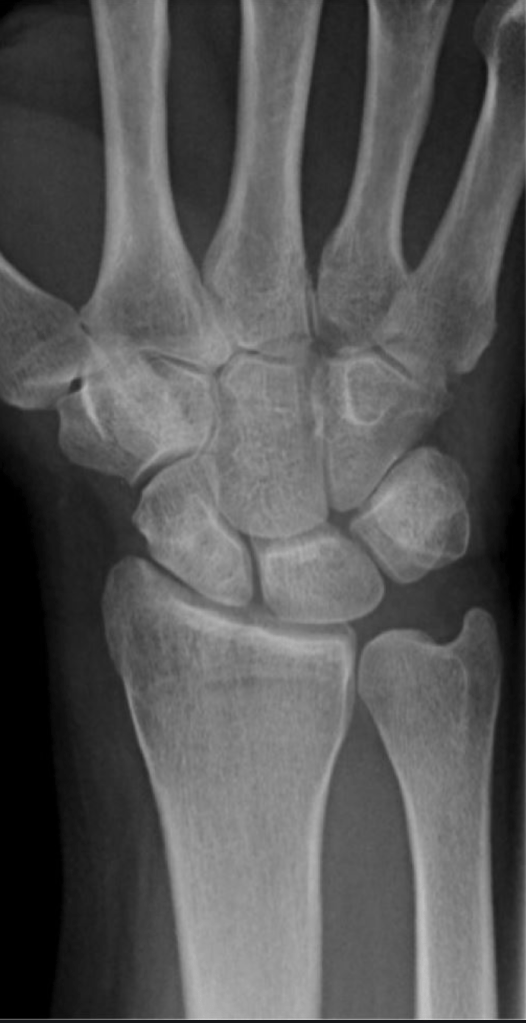

Kienbock’s disease of the lunate is a condition in which the normal blood supply to the lunate bone shuts off, and the bone is left without a blood supply. This causes the bone cells to die, and once enough bone cells have died, the structure of the bone starts to break down. The condition was first described in 1910, shortly after the development of X-rays, and it is named after the radiologist who described the condition, Robert Keinbock.

The lunate bone is one of 8 bones which make up the wrist joint, and is situated right at the centre of the wrist.

Pain in the wrist is the main symptom of Kienbock’s disease. This pain is situated over the lunate bone, and is usually dull and constant in nature. The pain can increase on use of the wrist and is generally better but not completely resolved with rest. As the condition progresses, the pain often increases, but in many people the condition is relatively static, and symptoms not too intrusive.